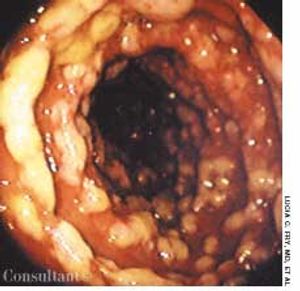

A 72-year-old man presented after several months of dyspepsia and 1 day of hematemesis. He was not taking NSAIDs.